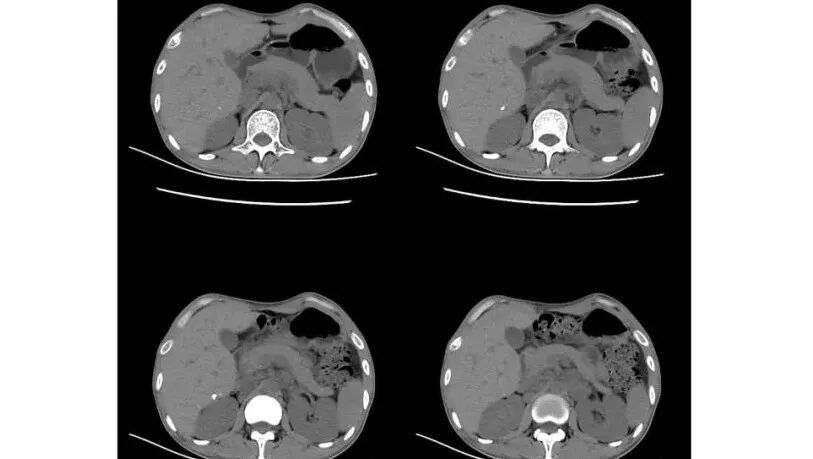

以下为2021-7-15日上腹部CT

影像与临床:1.青年男性,HlV阳性,颜面部皮疹(未提供皮疹图像)、发热(高热),实验室CRP、PCT高,T-Spot阴性。2.右肺下叶空洞结节,壁厚不均,边界清楚,其内线状影,未见液平及钙化,未见卫星灶,纵隔淋巴结增大,双侧腋窝见增大淋巴结。心腔内低密度提示贫血可能。肝脾影增大,未见结节影及块影。腹膜后见多发增大淋巴结。

综合分析:本例肺部影像学改变并不具有特征性,空洞性病灶须与多种疾病鉴别,但年轻HIV阳性患者,高热,皮疹,肝脾增大,纵隔、腋窝、腹膜后见多发增大淋巴结等都强烈提示马尔尼菲篮状菌感染的可能性。